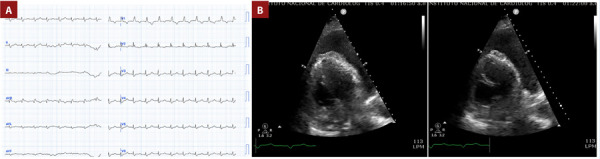

Systemic lupus erythematosus (SLE) is an inflammatory autoimmune disease with an important course due to systemic compromise. SLE is frequently associated with antiphospholipid syndrome, and pulmonary thromboembolism (PE) is particularly common. It is extremely rare for PE to be the initial clinical presentation and even more uncommon for it to coincide with cardiac tamponade, representing a challenge in diagnosis and management. We present a case of a 42-year-old woman with recurrent PE with severe pleural and pericardial effusion, hemodynamic instability, and cardiac tamponade. Laboratory workup revealed hypocomplementemia, leukopenia, negative SLE antibodies, and a positive lupus anticoagulant. This case emphasizes the importance of determining the etiology of PE, assessing risk classification, and implementing proper management, which are crucial for the patient's survival and outcome.